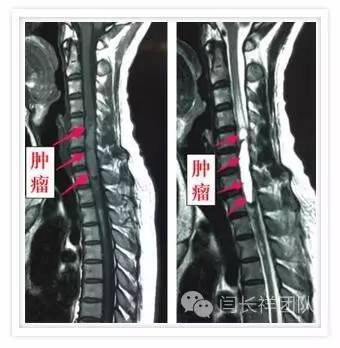

术前MRI示肿瘤位于髓内,显著压迫周围脊髓组织

颈5-胸1髓内占位,室管膜瘤